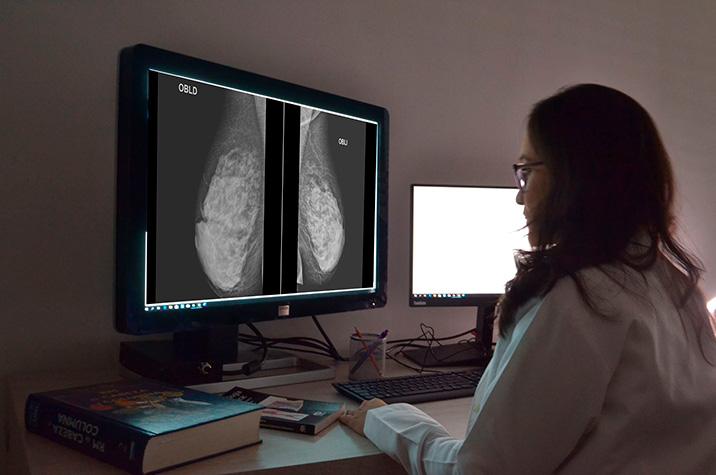

Participación en el primer rastreo mediante mamografía e incidencia y mortalidad por cáncer de mama en los 25 años siguientes

Este estudio demuestra que las mujeres que no participan en la primera detección representan un grupo importante con riesgo elevado de morir por cáncer de mama a largo plazo, lo que justifica la implementación de intervenciones específicas para mejorar la adherencia a las pruebas de detección y, así, reducir el riesgo de mortalidad. El aumento de mortalidad luego de 25 años de seguimiento fue del orden de 2 casos cada 1.000 participantes. BMJ, 24 de septiembre de 2025.